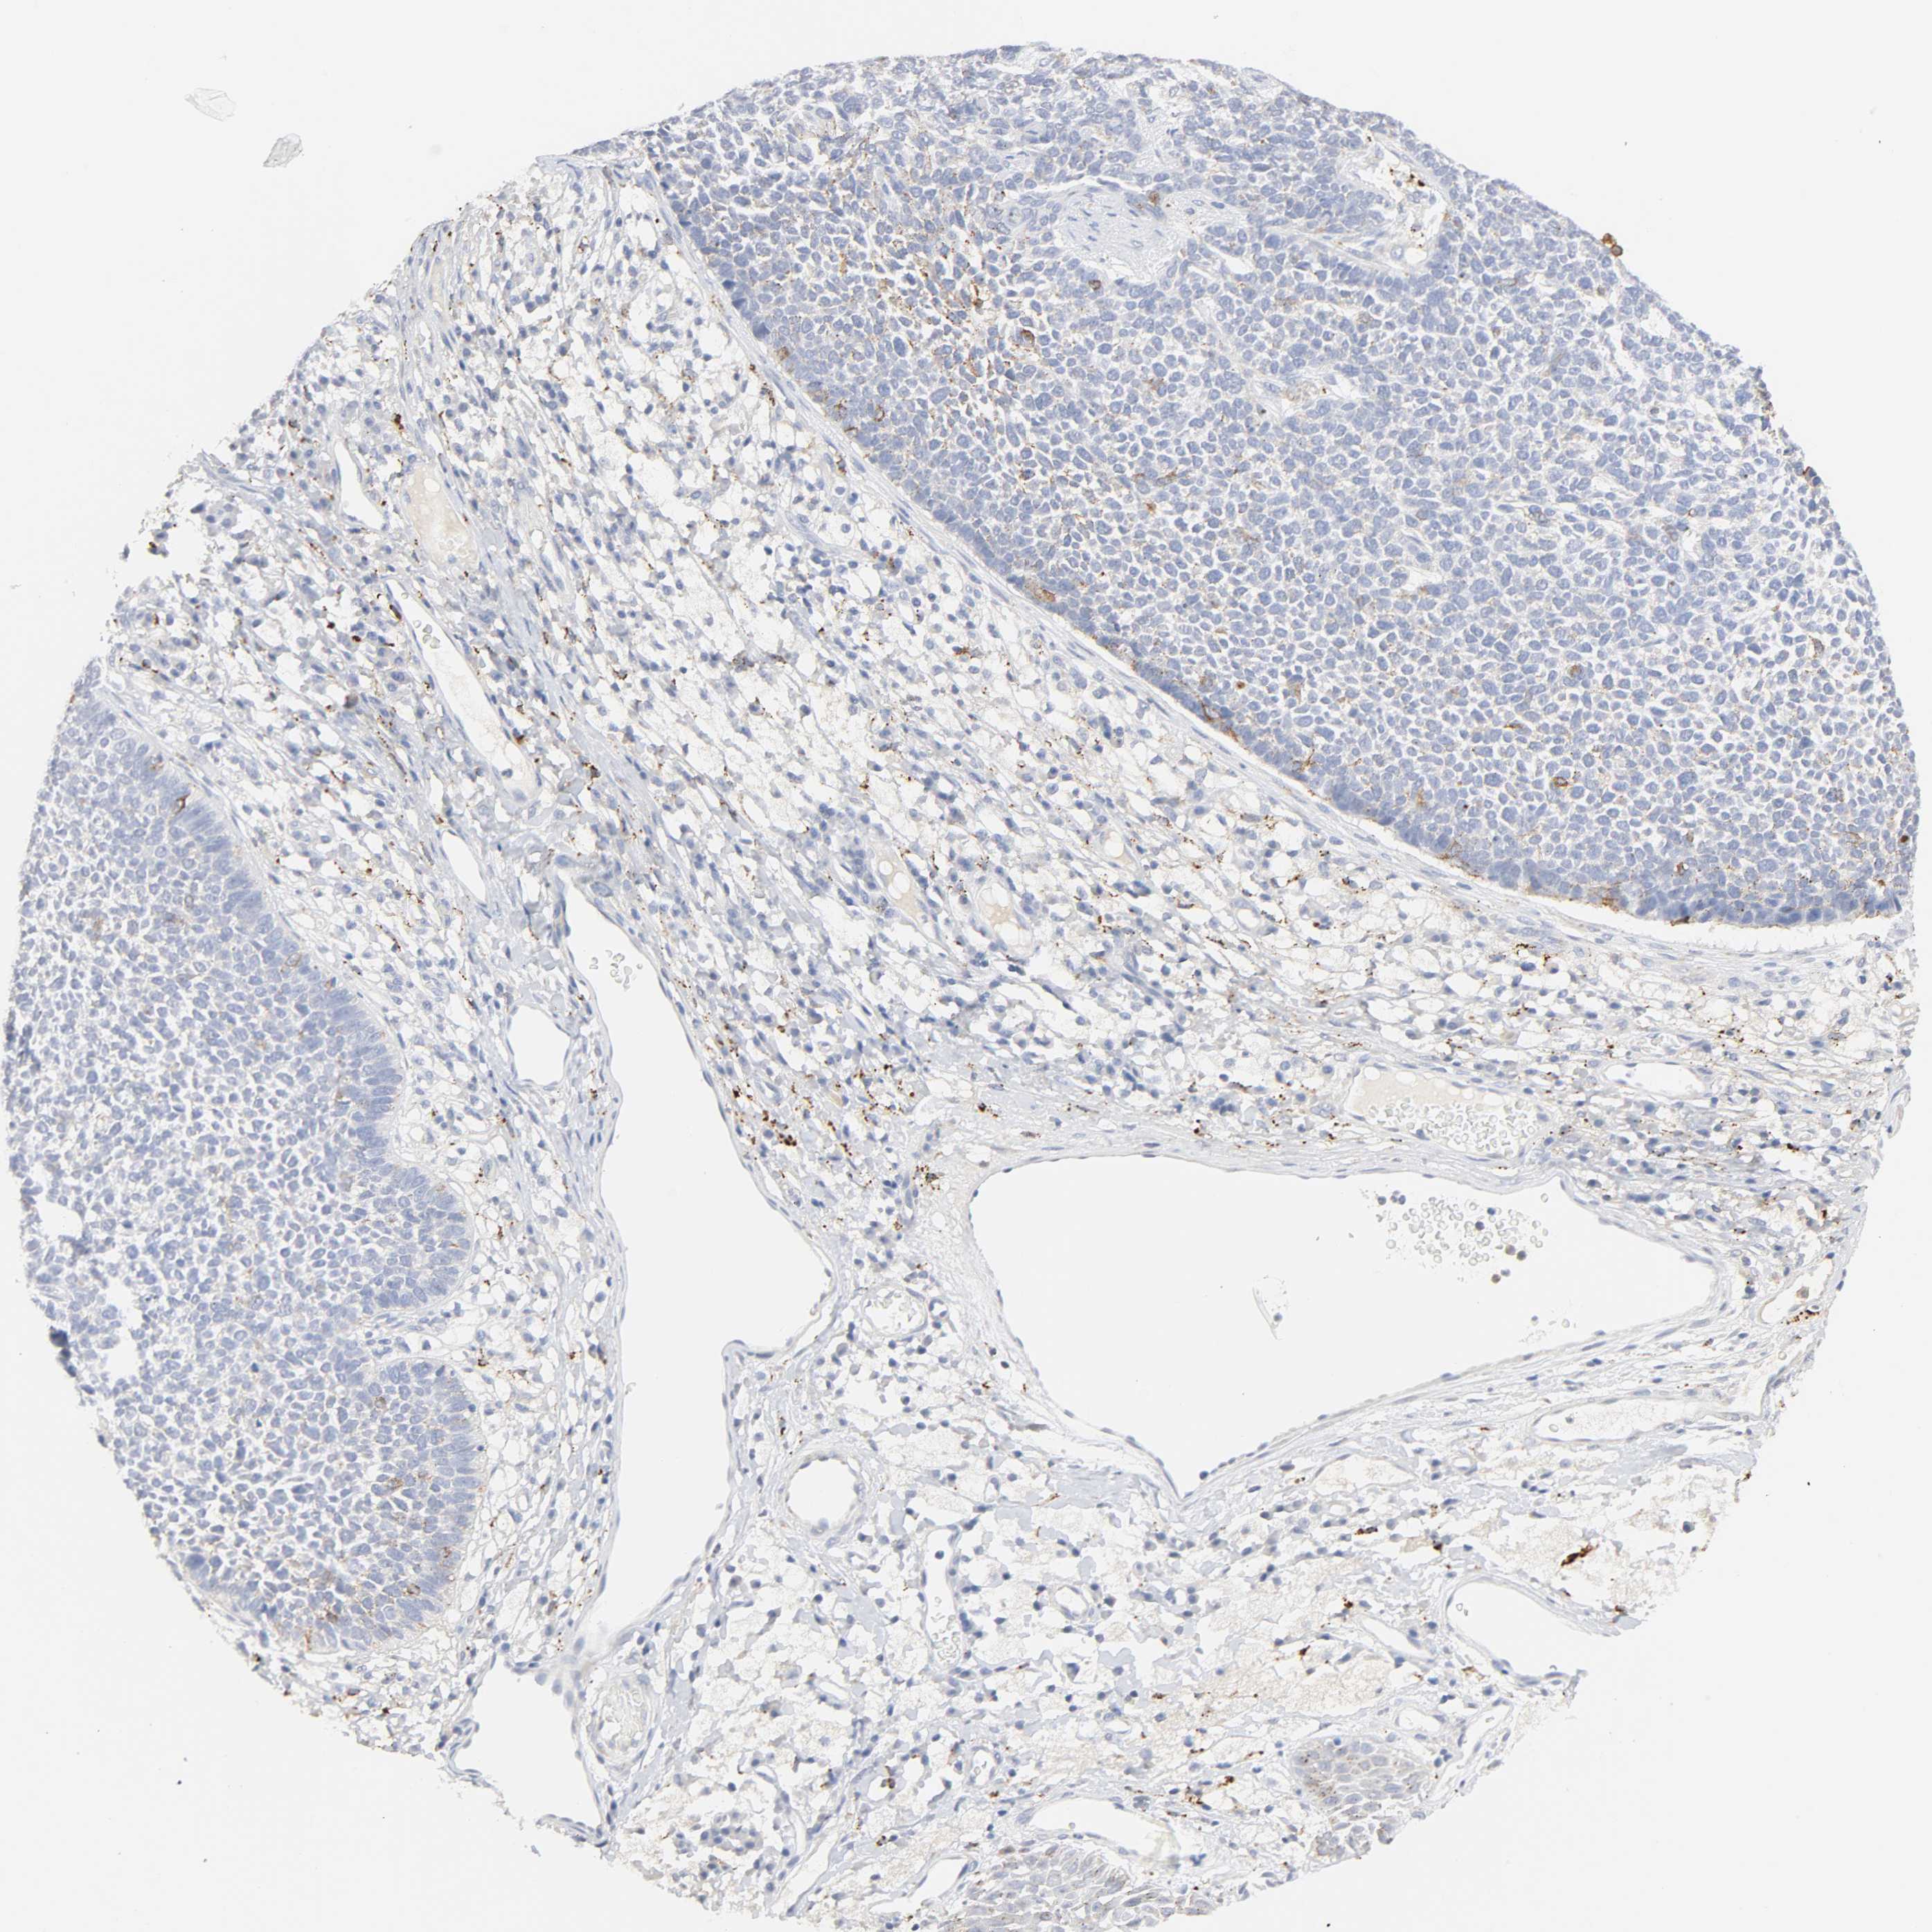

SKIN CANCER - Protein expressioni

A mouse-over function shows sample information and annotation data. Click on an image to view it in a full screen mode. Samples can be filtered based on level of antibody staining by selecting one or several of the following categories: high, medium, low and not detected. The assay and annotation is described here.

Antibody stainingi

Antibody staining in the annotated cell types in the current human tissue is reported as not detected, low, medium, or high, based on conventional immunohistochemistry profiling in selected tissues. This score is based on the combination of the staining intensity and fraction of stained cells.

Each image is clickable and will lead to virtual microscopy that enables deeper exploration of all samples and also displays staining intensity scores, fraction scores and subcellular localization as well as patient and tissue information for each sample.

Antibody HPA003756

Staining

High

Medium

Low

Not detected

Intensity

Strong

Moderate

Weak

Negative

Quantity

>75%

75%-25%

<25%

None

Location

Nuclear

Cytoplasmic/membranous

Cytoplasmic/membranous,nuclear

Basal cell carcinoma